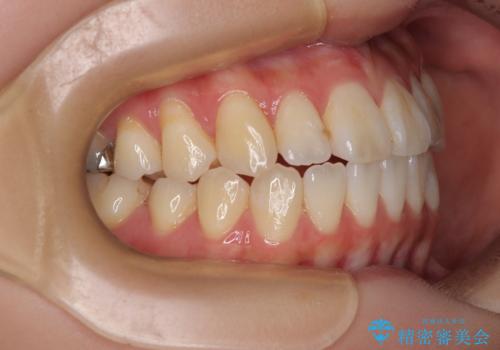

舌の突出癖が原因 インビザライン矯正による開咬改善

- 前歯の開咬を気にして来院された患者様です。

開咬の治療は、前歯を閉じるように動かすとともに、上下臼歯を圧下(骨内にめり込ませる)させることで進めて行きます。

インビザラインは臼歯の圧下を効果的に行えるため、インビザラインを用いて矯正治療を行うこととしました。

オープンバイトは舌の突出癖により誘発され、治療後も突出癖が残っている容易に後戻りしてしまいます。

治療期間を短縮するためにも、舌突出癖の改善が極めて重要となります。

特にインビザラインではIPRという歯と歯の間を削る処置を多用するため、後戻りによりスペースが生じやすくなるため、治療初期段階での舌のトレーニングが必須となります。